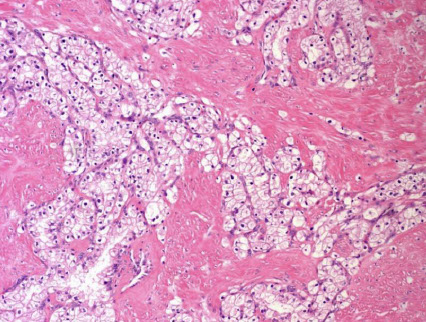

Membranous Glomerulonephritis (MGN)

- aka diffuse membranous glomerulopathy/nephropathy

MCC of adult nephrotic syndrome; 85% idiopathic though can be attributed to drugs / medications, infx, SLE (up to 1/5 SLE pts; though SLE can produce any kind of glomerular disorder), solid tumors ( GI, lung and prostate); mainly IgG4 found

Mech: most caused by abs (IgG4) against phospholipase A2 Receptor (PLA2R), an antigen on the basal surface of the visceral glomerular epithelial cell

LM: diffusely thick glomerular capillary walls c no cell prolif change; can have eosinophilic protein resorption droplets in tubular epithelial cells from high-grade proteinuria

- can have mesangial prolif chronically

- glomerular tuft can adhere to Bowman's capsule (as in tip changes), but this doesn't change the dx

- must confirm using immunohistology, see basement membrane spike formation on silver stain (looks like beard stubble)

EM: "spike and dome" appearance c subepithelial deposits of normal GBM going through immune deposits seen c silver stain

IF: diffuse granular deposits of IgG +/or C3 on GBM

Px: 1/3 of pts c renal failure or die at 10 yrs, 1/3 recover, 1/3 stay the same c proteinuria